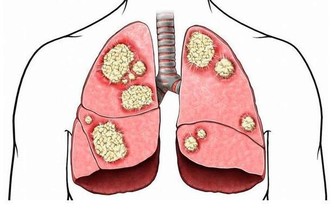

6、消化道不適 這是最常見的肝病癥狀, 大多數肝病都會出現, 比如:噁心、厭油膩、食慾差、全身乏力等, 可出現嘔吐,腹瀉,脾腫大等癥狀。 此類癥狀也可能與慢性肝病引起的 肝原性潰瘍病, 門靜脈高壓性腸病等有關。 7、肝腹水 肝腹水一般在肝病晚期或病情極為嚴重時才會出現, 如肝硬化出現肝腹水,表示已經進入肝硬化晚期。 出血傾向: 肝病出血現象體現在肝功能減退,使凝血因子合成減少所致。 容易引起肝病患者牙齦出血、痔瘡出血、胃腸道出血等, 且出血時難以止住。 門靜脈高壓: 門脈高壓是指門靜脈係統壓力升高。 常引起食管胃底靜脈曲張,是造成消化道出血的主要原因。 一旦發生出血,結合出血傾向病情往往比較兇險, 是肝病(主要指肝硬化、肝癌晚期)死亡的主要原因之一。 8、肝性腦病 這是肝病發展到終末期的表現, 癥狀極為兇險,是造成肝病死亡最主要的原因。